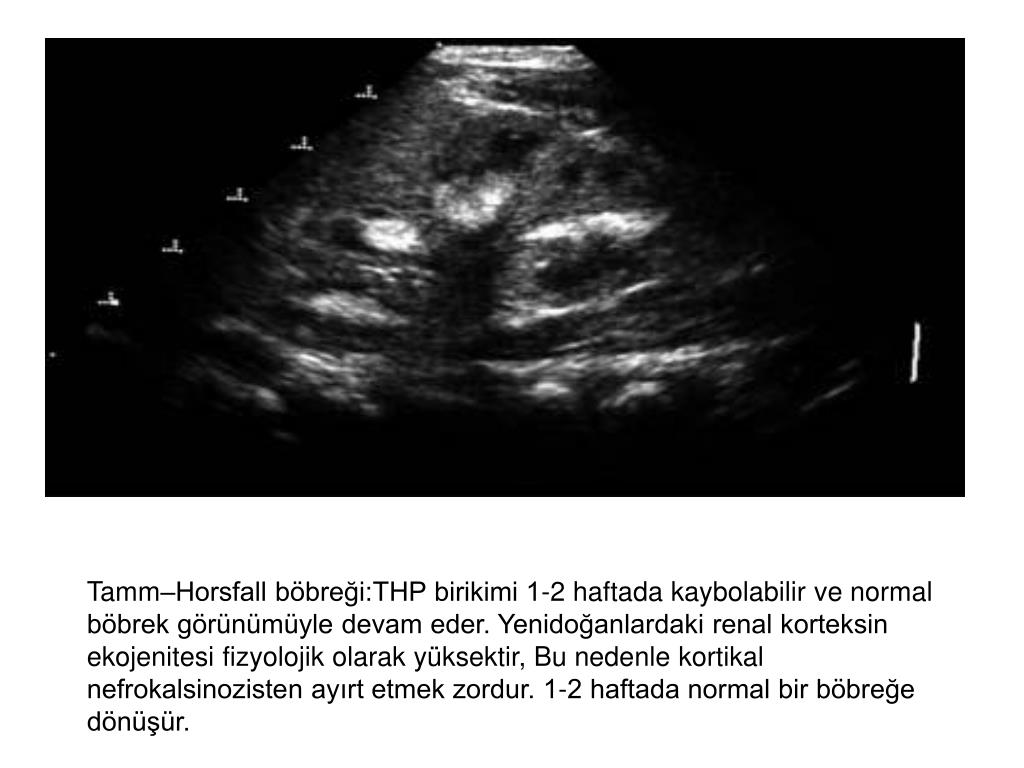

12. Preterm bir infantın hiperekoik böbreği

13. Tamm–Horsfall böbreği:THP birikimi 1-2 haftada kaybolabilir ve normal böbrek görünümüyle devam eder. Yenidoğanlardaki renal korteksin ekojenitesi fizyolojik olarak yüksektir, Bu nedenle kortikal nefrokalsinozisten ayırt etmek zordur. 1-2 haftada normal bir böbreğe dönüşür.